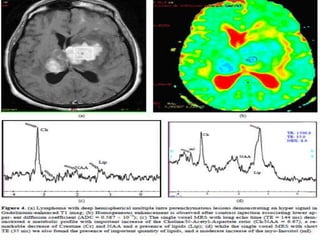

A 26-year-old male with low grade tumor (oligodendroglioma, WHO grade

II) was misdiagnosed as high grade tumor due to peculiar tumor histopathology of

oligodendroglioma. A, B and C, Focal cystic encephalomalacic change is noted in the

right frontal lobe with peripheral enhancing portion (A: T2-weighted image, B: FLAIR

image, C: postcontrast T1-weighted image). D and E, MR spectroscopy of the lesion

shows markedly increased choline and lactate with decreased NAA, interpretating as

high grade tumor.